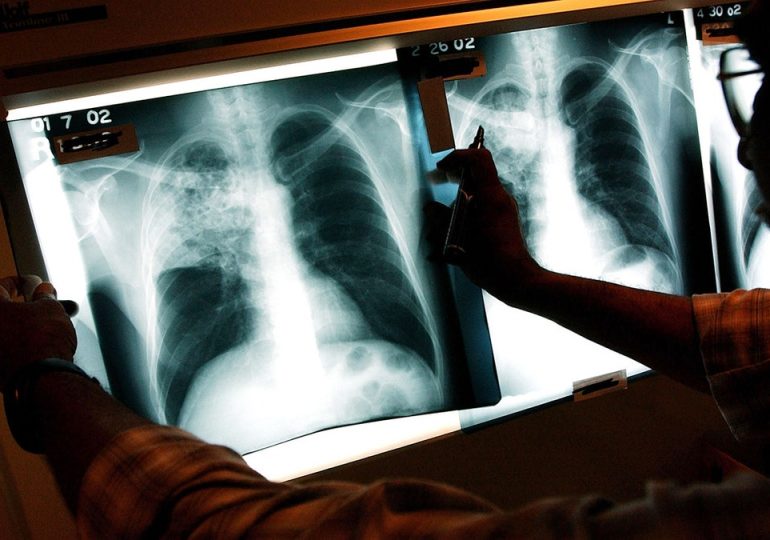

The x-ray of a TB patient in New York in 2002. (Spencer Platt/Getty Images)